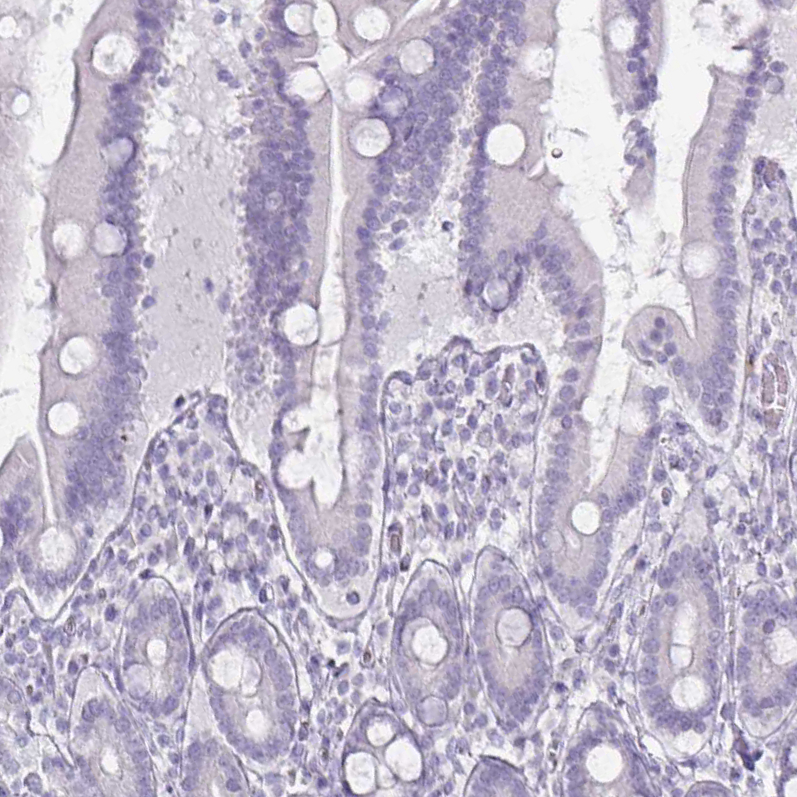

Immunohistochemistry analysis in human thyroid gland and liver tissues using AMAb90523 antibody. Corresponding TG RNA-seq data are presented for the same tissues.